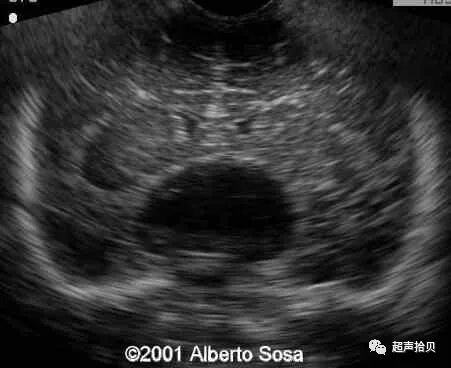

图4:图4A,25次妊娠时获得的横向声像图。 病变最初被诊断为蛛网膜

囊肿(C)伴有出血(H)。 B,妊娠26孕妇的产前MRI T2加权横向图像显示硬脑膜窦性畸形(D)合并血栓形成(T)

27岁妊娠24周的胎儿进行常规扫描,在胎儿脑的中线上或第三脑室区域检测到直径约25mm且无多普勒流的圆形无回声肿块。

侧脑室大小稍微增加(11mm),并且没有看到其他异常。

图1A,妊娠24周后胎儿的矢状面,中线囊肿直径25毫米。 B,胎儿的横断平面脑室扩大,中线囊肿。